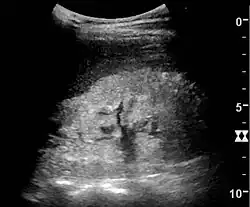

Ultrasound

Kidney ultrasonography is useful for diagnostic and prognostic purposes in chronic kidney disease. Whether the underlying pathologic change is glomerular sclerosis, tubular atrophy, interstitial fibrosis, or inflammation, the result is often increased echogenicity of the cortex. The echogenicity of the kidney should be related to the echogenicity of the liver or the spleen. Moreover, decreased kidney size and cortical thinning are often seen, especially when the disease progresses. However, kidney size correlates to height, and short persons tend to have small kidneys; thus, kidney size as the only parameter is unreliable.[63]